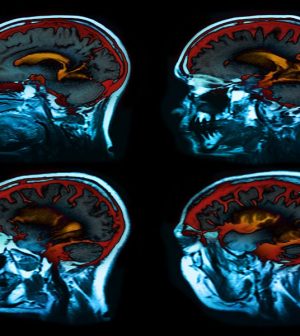

The study included nearly 200 healthy older people who underwent MRI brain scans three times over a period of two years. The researchers assessed more than 450 features of brain anatomy, including total brain volume, volumes of gray and white matter, and thickness of the cortex.